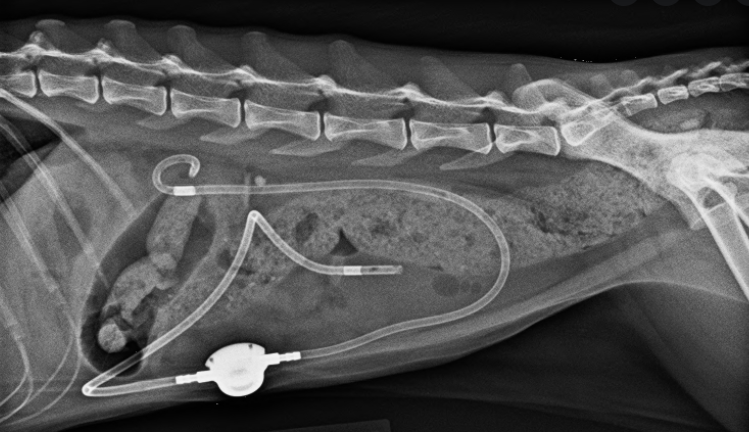

비교적 최근에 도입되어 국내에서도 많이 시행되고 있는 요관스텐트 SUB( subcutaneous ureteral bypass ) 이다.

이 논문은 본 수술을 진행한 총 81마리의 고양이를 대상으로 수술 전후로 이상 여부에 대한 평가를 한 논문이다.

결론은 좋다. 해도 된다라는 의견이다.

눈대중으로 봐도 시술 2년정도 경과에서 절반정도가 사망하였고 2000일 넘게 생존한 고양이도 40%는 된다는 의미이다.

물론 신부전이 있는 경우 다른 요인에 의한 환자에 비해 사망률이 초기 급격하게 늘어나는 경향이 있다. 신부전이 동반된 경우 보호자 교육이 절대적으로 필요하다는 말이 된다.

요관 폐색의 원인이 협착인경우 3년내 사망율이 매우 높으나 결석때문에 막힌 경우에는 전반적으로 사망가능성이 낮다는걸 의미한다.